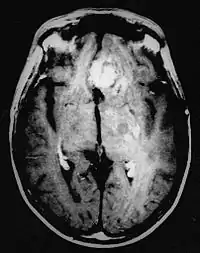

Diagnóstico por imagen y glioblastoma

La TC muestra una lesión de morfología irregular, predominantemente hipodensa y fuertemente dishomogénea, debido a la presencia de grandes áreas necróticas de más clara hipodensidad y de áreas sólidas hiperdensas. Estas últimas son la expresión de un rápido crecimiento y por lo tanto de una elevada malignidad. Son frecuentes las zonas hemorrágicas, que van desde pequeños focos a grandes áreas hemáticas que pueden cubrir toda la lesión. Es característica la morfología en "mariposa" si el tumor se asienta en ambos hemisferios a través del cuerpo calloso.

Tras la aplicación de contraste aparecen gruesos anillos alrededor de las áreas necróticas. En la RM, la parte sólida aparece hipointensa en T1 e hiperintensa en T2 con zonas de señal más elevada en las partes de mayor celularidad. Las áreas necróticas, hiperintensas en T2, pueden presentarse hipo-, iso- o hiperintensas en T1 en función del contenido proteico o de productos de la degradación de la hemoglobina. El realce tras el contraste suele ser intenso e irregular en la periferia del tumor e identifica sobre todo la componente celular "proliferativa" de la neoplasia. Son comunes las áreas puntiformes y serpiginosas de ausencia de señal de flujo, asociadas a la presencia de una neovascularización rica. Estos vasos de neoformación patológica carecen de barrera hematoencefálica, lo que explica tanto la abundante impregnación como el edema vasogénico perilesional (véase la sección anterior), debido al paso de líquido al medio extracelular.[71][72]